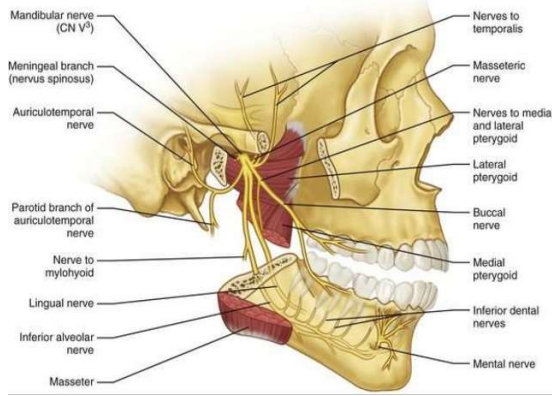

Nerve contents of the infratemporal fossa

mandibular nerve and its branches:

inferior alveolar nerve

buccal nerve

lingual nerve

(nerves to msucles of mastication)

What is inferior alveolar nerve block

anaesthetic injected around the mandibular foramen which blocks the inferior alveolar nerve

What is mandibular nerve block

anaesthetic injected adjacent to the nerve as it enters the infratemporal fossa

Which nerves are affected by mandibular nerve block

inferior alveolar, lingual, buccal and auriculotemporal